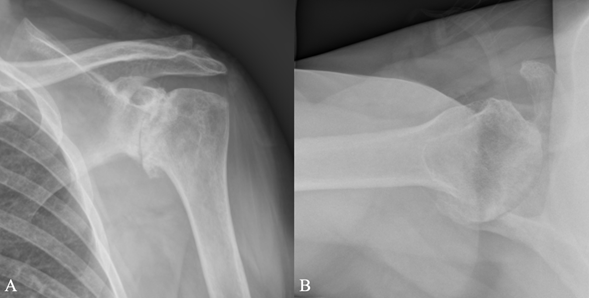

A 59-year-old female presented with a history of chronic left shoulder pain and stiffness. In addition to classic osteoarthritic symptoms, she reported an atypical pain described as a constant, deep-seated, “burning” sensation in the chest and shoulder region that ranged in severity from 6/10 at its best to 9/10 at its worst. This pain combined with debilitating weakness in the upper back and shoulder muscles had progressed to interfere with activities of daily living. This burning sensation in the chest and shoulder was not reproducible on physical exam, but there was palpatory tenderness inferior to the acromioclavicular joint, long head of biceps and anterior supraspinatus consistent with shoulder osteoarthritis and rotator cuff damage. During both passive and active range of motion exams, the patient was limited to 30 degrees of shoulder forward flexion, 30 degrees shoulder abduction and 0 degrees of both internal and external rotation, with palpable and audible crepitus. Pain was noted with all provocative maneuvers. She was neurologically intact in the axillary, radial, median, and ulnar nerve territories, with normal sensation to light touch, proprioception and two-point discrimination. Diffuse muscle atrophy was noted throughout her left shoulder on physical exam. She had equal radial and brachial pulses when compared to the contralateral asymptomatic arm. X-rays of the left shoulder revealed advanced, end-stage glenohumeral osteoarthritis with significant circumferential osteophytosis (Figure 1A &1B). As it was determined unlikely for these symptoms to be caused by isolated shoulder osteoarthritis and to help guide further management, MRI scans were ordered which demonstrated some thinning of the supraspinatus tendon, with Goutallier Grade 1 fat atrophy, and a degenerative long head biceps tendon. Additionally, a large cystic structure originating from the biceps tendon was noted (Figure 2).

Figure 1 Preoperative plain radiographs of left shoulder in both A) anteroposterior and B) axillary views.